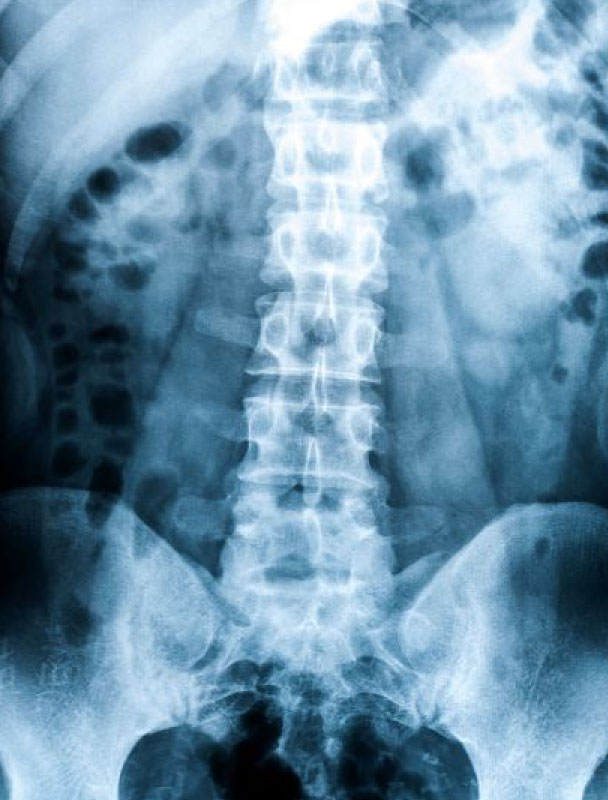

X-ray Services

Broke or dislocated a bone? We will bring our x-ray machines to your location to take x-rays of your injury.